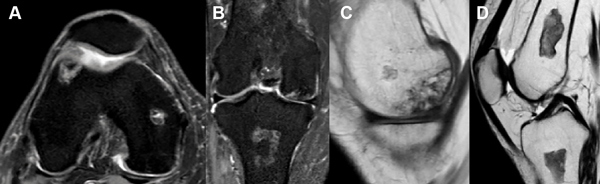

La resonancia magnética (RM) de la rodilla derecha evidenciaba imágenes compatibles con infartos óseos en metáfisis femoral, metáfisis tibial, tróclea femoral externa y meseta tibial homolateral que corresponde a un estadio II de la clasificación de Ficat y Arlet (fig. 2). En la RM de la rodilla izquierda se observaban múltiples infartos óseos en ambas mesetas tibiales, metáfisis tibial y metáfisis femoral, junto a foco de osteonecrosis en cara inferior del cóndilo femoral interno (fig. 3) que corresponde a un estadio III de la clasificación de Ficat y Arlet.

Figura 2: Resonancia magnética de rodilla derecha. A) Corte axial. B) Corte coronal. C y D) Cortes sagitales con focos osteonecróticos en ambos cóndilos femorales y en metáfisis femoral y tibial.

Figura 3: RM de rodilla izquierda. A) Corte axial. B) Corte coronal. C y D) Cortes sagitales. Múltiples infartos óseos difusos. Pequeño foco de osteonecrosis en la cara inferior del cóndilo femoral interno. Mayor afectación en mesetas y metáfisis tibial.